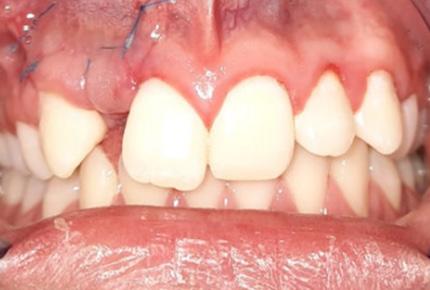

Inclusión dentaria por un odontoma compuesto

Dental inclusion by a compound odontoma

Javier Burgos, Francis Argandoña, Gabriela Adriana Lara...................................................................107-115